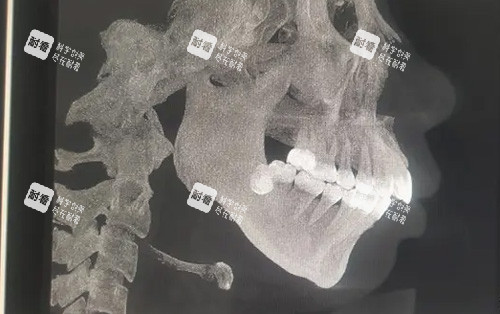

術(shù)前精細(xì)建模:通過(guò)CT掃描和3D數(shù)字建模,提前模擬手術(shù)路徑,避免神經(jīng)損傷;

小牛的故事,堪稱“頜面逆襲教科書(shū)”。她從小因上頜發(fā)育過(guò)度、下巴后縮被同學(xué)起外號(hào)“月亮臉”,工作后因形象自卑不敢參加社交活動(dòng)。2024年初,她找到艾偉健醫(yī)生,經(jīng)過(guò)詳細(xì)評(píng)估后,醫(yī)生制定了“上下頜根間截骨術(shù)+頦成型術(shù)”方案。術(shù)后3個(gè)月復(fù)查時(shí),她的臉型從“凸面型”變成流暢的“直面型”,連同事都追問(wèn)“是不是偷偷去做了醫(yī)美”。